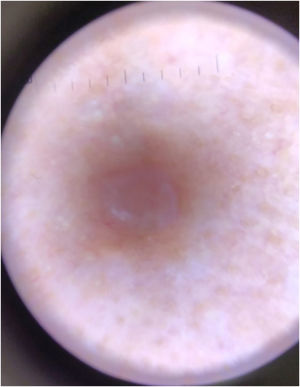

A 31-year-old woman presented with asymptomatic papular lesions on the nasolabial folds, nose, and forehead, which had first appeared during the first month of life and progressively increased in number over time (Fig. 1). Lesions began perinasally and later involved the scalp and extremities. No additional skin tumor, such as cylindroma or spiradenoma, was detected. The patient denied a family history of similar lesions, and there was no known consanguinity. Physical examination revealed multiple, firm, asymptomatic, skin-colored papular lesions of 0.2‒0.4 cm in diameter on bilateral nasal margins and forehead (Fig. 1). Multiple soft nodular lesions were observed on the occipital region and scalp (Fig. 2), along with a 1.4 cm nodule on the extensor surface of the right elbow and hyperkeratotic papules on the dorsum of the left toes. Dermatoscopic examination revealed a regular architecture with regular borders, thin, irregular vessels located peripherally, and opaque white areas on the lesion, which were suggestive of trichoepithelioma (Fig. 3). No dermoscopic signs of basal cell carcinoma (BCC) or sebaceous adenoma were present. Laboratory investigations showed no abnormalities. A punch biopsy was obtained from a lesion on the nasal margin with clinical differential diagnoses including adenoma sebaceum, syringoma, and trichoepithelioma. Histopathological examination disclosed features consistent with trichoepithelioma, characterized by basaloid cell islands, papillary mesenchymal structures, and cysts containing lamellar keratin within the dermis. DNA sequence analysis covering all coding exons (9–20) and exon-intron boundaries of the CYLD gene was performed using bidirectional capillary Sanger sequencing, as previously described.2,3 This analysis revealed a heterozygous variant, NM_015247.2:c.2687 G > G>T (p.Gly896Val), located in exon 20, with other previously reported mutations also shown in Fig. 4.4,5 The patient was referred for genetic counselling. Due to financial constraints, laser treatment was not performed. Instead, selected lesions were treated with cryotherapy and electrocautery; however, these interventions were discontinued due to unsatisfactory cosmetic results. The patient continues to be under regular clinical follow-up.